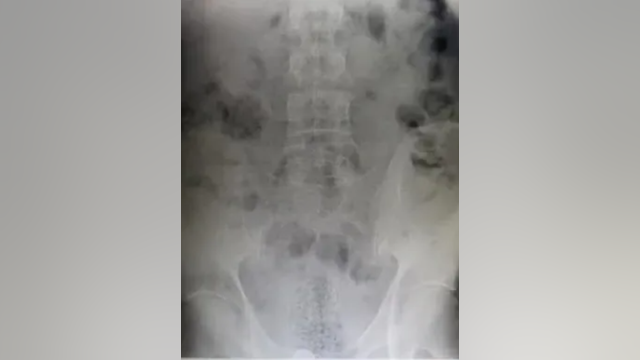

Texas Border Patrol finds 1/3lb fentanyl hidden in rectum of border crosser

CBP officers continued to monitor the man while he was under medical care, and he eventually passed a bundle.